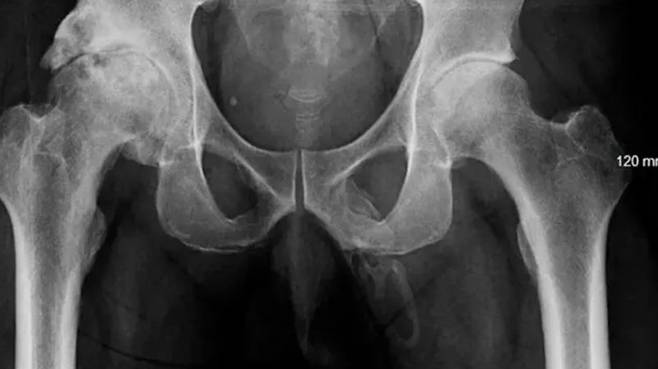

분비물은 없었고 전립선도 붓지 않았으나 음경에 통증을 느끼는 상황에서, 의료진은 골절 여부 확인을 위해 A씨의 골반 X-ray를 촬영했고 놀라운 결과가 나왔다. 음경 안에서 뼈와 비슷한 구조물이 발견된 것.

음경에 칼슘이 축적돼 뼈처럼 단단해지는 ‘석회화’ 과정이 관찰된 것으로, 의료진은 "음경 전체에 걸친 음경 골화증 진단이 의심됐다"라고 소견을 밝혔다.

음경 골화증은 음경의 연조직에 축적된 칼슘으로 뼈와 같은 비골격 구조물이 생기는 희귀 질환이다. 지금까지 보고된 대부분의 사례는 국소적 골화인 반면, A씨의 사례는 음경 전체에 골화가 존재한다는 점이 특이하다. 음경 전체가 영향을 받는 케이스는 매우 드물다.